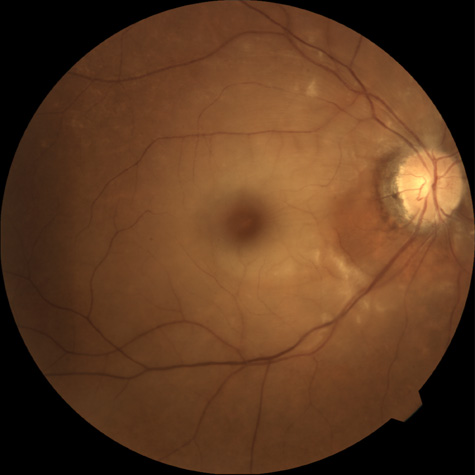

Hypoperfusion retinopathy is characterized by dot and blot hemorrhages in the midperiphery of the fundus, by venous tortuosity and engorgement, by microaneurysms, and by the occasional sludging of blood within the veins. Fluorescein angiography may show areas of capillary nonperfusion; it may also show microaneurysms in the midperiphery and slow arm to retina or arteriovenous transit time (Fig. 9A and 9B).174 The condition does not usually affect the posterior pole, and patients typically have normal visual acuity, although an occasional patient may have macular edema.174 The entire periphery of the eye is usually affected, although there may be more hemorrhages in one quadrant than another. Patients occasionally experience ocular discomfort or eye pain despite normal intraocular pressure. Reduction of the ophthalmic arterial pressure is a pathognomonic feature. Disc edema and disc collaterals are generally not present. The electroretinogram shows abnormalities in both the a- and b-waves (see Fig. 9C).

Fig. 9. Intravenous fluorescein angiogram of a patient with hypotensive or hypoperfusion retinopathy. A: There is a marked delay in the choroidal and retinal filling. B: In the recirculation of the angiogram, there is a characteristic staining of both arteries and veins. C: Electroretinogram shows normal a- and b-waves in the normal right eye (upper tracing) and marked redirection of the a- and b-waves in the affected left eye (lower tracing).